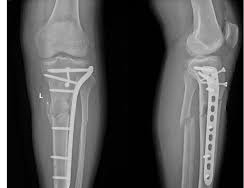

We excel in managing complex injuries, from pelvic fractures to spinal trauma, with a growing referral base from other states.

Orthopaedic Trauma Surgeons are unique in that they specialize in complex injuries to bones, joints and soft tissues (like muscles, tendons and ligaments) throughout the entire body. Many orthopaedic specialists specialize in just one body part. Others may provide more general care but won’t treat more acute fractures, which are physically more difficult to fix. Orthopaedic trauma physicians, however, receive training in the field of orthopaedic surgery with a special focus on the treatment of fractured bones and joint realignment to promote the safe recovery and return of functionality to injured body parts. So, they often treat patients with multiple broken bones, compound fractures and fractures near a joint (like a hip or knee).Orthopaedic trauma surgeons are able to follow patients through all stages of recovery and enlist the help of other specialists, if needed, to treat complex cases. By maintaining open communication with all providers, they are able to ensure each patient receives the care needed to resume a full and active lifestyle.

The centre of excellence offers extensive expertise in: